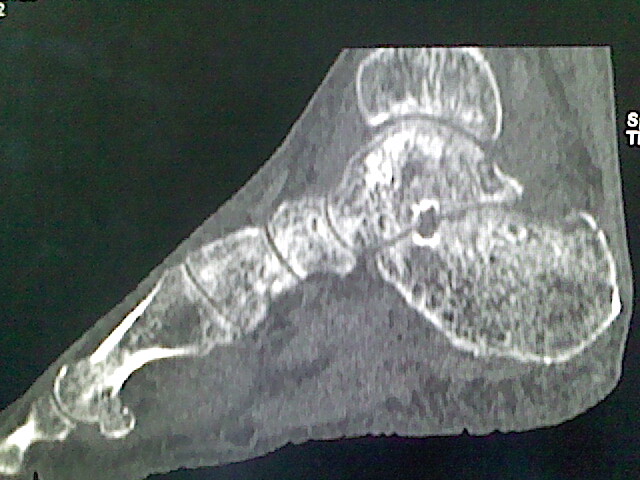

标题: CT16814:男,76岁,左小腿疼痛,不能站立 大家给看看 [打印本页]

男,76岁,左小腿疼痛,不能站立

本例骨质改变主要表现为滑膜或韧带区的骨侵蚀融解(胫腓联合区骨质破坏无硬化边),距骨后部骨质破坏区有硬化边及死骨样改变.所以,本例考虑关节结核可能性大,绒毛膜结节性滑膜炎多发于中年,且极少见于膝髋以外的关节,骨质硬坏也以压陷吸收为主,有明显的硬化边,骨膜增生呈结节状(可以mr鉴别),所以本例暂除外.

另不除外可引起相似表现的其他炎症如布氏杆菌性关节炎等